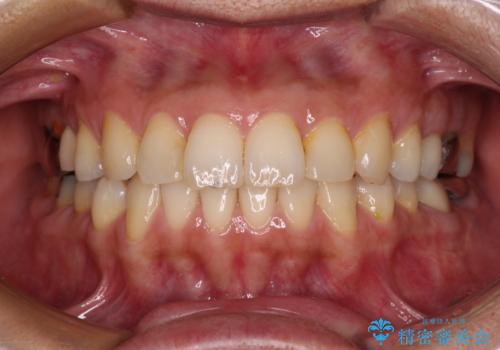

矯正治療後には、左下奥歯の症状がないことを確認し、セラミッククラウンにて補綴治療を行うこととしました。

矯正治療後のレントゲン写真では、根尖部に認められた病変(骨の溶けていた像)は消失していることが分かりました。